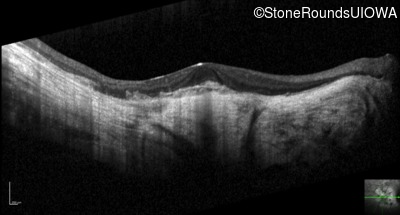

Optical Coherence Tomography - Right - 20/100 -2

Exemplar / OCT Stack

OCT Stack